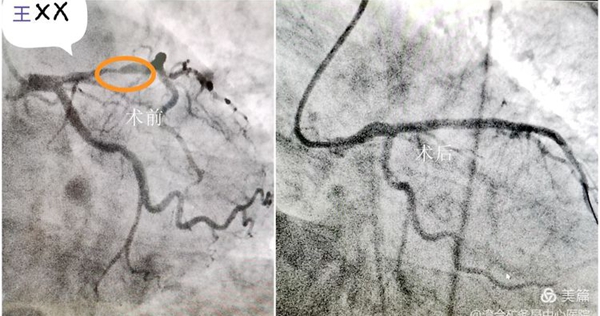

案例2:冠状动脉造影+球囊扩张术(PTCA)

患者周某,男,69岁,因“发作性胸闷、胸痛10天,快行及上楼加重”入住该院心血管内科。入院后,张建群医生立即接诊,并给予急查心电图、心肌酶谱、肾功、电解质等检查,初步诊断为“冠心病”。经过充分的术前准备,心血管内科介入中心团队为患者在介入导管室内成功实施冠状动脉造影术,提示三支病变,前降支中段闭塞,旋支近段95%狭窄,右冠近段80%狭窄,开通前降支后造影提示前降支血管细小,行球囊扩张术,术后患者生命体征平稳,安全返回病房,目前病情稳定。